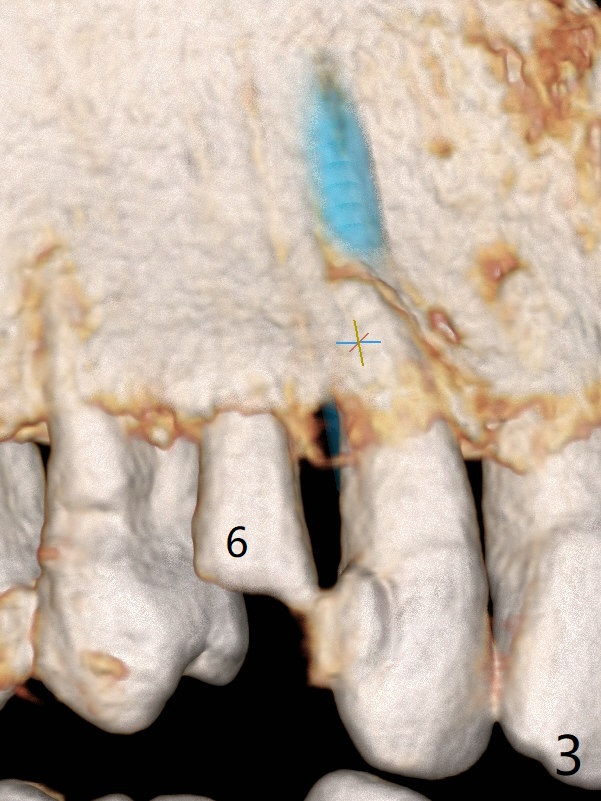

Lateral Implant/Canine Post

The tooth #7 (52 y/o, M, smoker) has mobility 2 months post #24/26, 30 implant placement without provisional (Fig.1,2) and seems to be necessary to be extracted for implant, while post and crown will be placed at #6 (Fig.3).